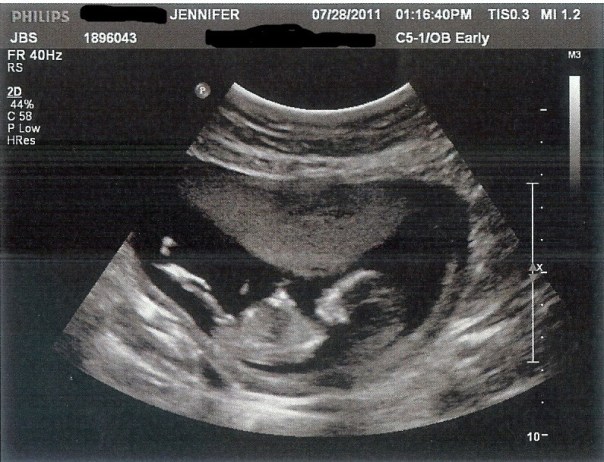

The following day we had my Nuchal Translucency scan. It’s a test that can only be done between 11 and 13 weeks where they measure the back of the baby’s neck to see if it’s thickened which is common in babies with Down Syndrome. They also do a blood test and these two tests together will tell you the risk factor for your baby. We just like to get an extra peek at the baby and 12 weeks is such a great time for an ultrasound because the little ones are moving like crazy even though you can’t feel it and they have tons of space to bounce around it.

I was 12 weeks 4 days at this scan (I was 12w1d at Adaline’s scan) and this baby was completely different from Adaline. Adaline moved like crazy…so much so that it took them the longest time to get her calm enough to measure her neck. She literally bounced off of the walls of my uterus and did flips and everything. This baby was very laid back. The movements were all small wiggles and hand movements, nothing big. It was so interesting to see how different this baby was compared to my daughter. Even though this baby stayed pretty still (s)he was still in the wrong position for the test and we had the opposite problem. The tech had me coughing and smacking my belly to try to get the baby to move into a different position and each time it would just fidget every so slightly as if to say, “Leave me alone! 5 more minutes, mom!”

Right after the scan they let me know that the neck looked normal but to remember that the blood test is important and then I went upstairs to have blood drawn. I’ve read online that many women get a finger prick for this test but both times I’ve had blood drawn from my arm. The hospital called a few days later to let me know that all of the test results looked normal and to give me the risk factor, which I don’t remember the exact number, but it was very low.